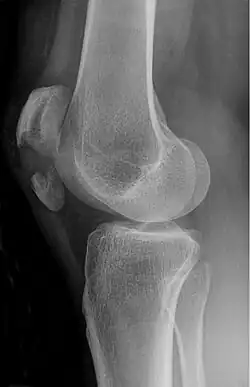

A fracture of the patella seen on a lateral view